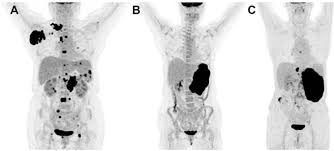

In this article, we discuss the different types of bone marrow cancer, including their symptoms and how to treat them. Both tests are basic and safe for the majority of people. Discover 10 common bone marrow cancer symptoms at 10faq health and stay better informed to make healthy living decisions. Doctors will check your bone marrow to see if it's making normal amounts of blood cells. This is called a bone marrow test. To keep track of how well cancer treatments are working and check cancer type: Bone cancer most commonly affects the long bones in the arms and legs. Bone marrow biopsy is a diagnostic procedure where a small amount of bone marrow is extracted from hip region and tested for abnormal blood cell the sample is then sent to labs to check for any abnormalities, including cancer. How does the search for a bone marrow or blood stem cell donor work? This test is done with anesthesia to minimize discomfort or pain. This procedure might be called peripheral stem cell transplant or cord blood transplant, depending on where the stem. How to understand your cancer pathology results. Bone marrow contains a large number of stem cells.